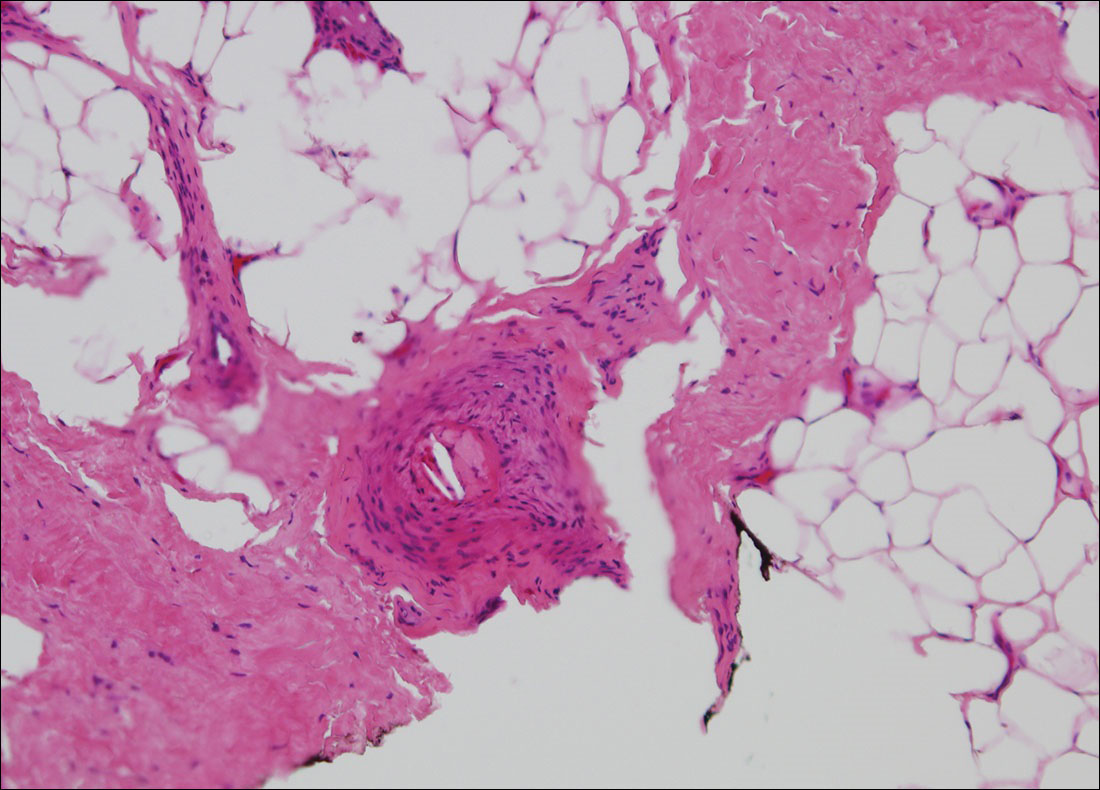

The clinical manifestation suggested blue toe syndrome. A variety of causes for blue toe syndrome are known such as embolism, thrombosis, vasoconstrictive disorders, infectious and noninfectious inflammation, extensive venous thrombosis, and abnormal circulating blood.1 Among them, only emboli from atherosclerotic plaques give rise to typical cholesterol clefts on skin biopsy (Figure 1). Such atheroemboli often are an iatrogenic complication, especially those caused by invasive percutaneous procedures or damage to the arterial walls from vascular surgery. However, spontaneous plaque hemorrhage or shearing forces of the circulating blood can disrupt atheromatous plaques and cause embolization of the cholesterol crystals, which was likely to be the case in our patient because no preceding trigger events were noted.